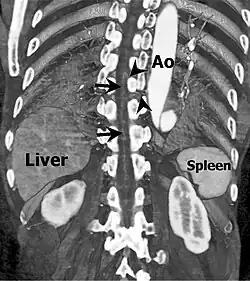

Das Rückenmark wird auf Höhe der Brust- und Lendenwirbelsäule hauptsächlich durch direkte Äste der Brust- oder Bauch-Aorta (Rückenmarksäste, Rami spinales) versorgt. Die Adamkiewicz-Arterie ist eine besonders große dieser Arterien. Sie hat einen Durchmesser von 0,6 bis 1,8 mm und ist mit der längs des Rückenmarks verlaufenden Arteria spinalis anterior verbunden.[1][2]

Der häufig variierende Verlauf der Adamkiewicz-Arterie ist insbesondere bei der Wirbelsäulenchirurgie oder bei der chirurgischen Behandlung von Aortenaneurysmen von Bedeutung.[1] Verletzungen der Arterie können zu einer Blutarmut (Ischämie) im Rückenmark und damit zu Lähmungen führen.[2] Deshalb werden vor solchen Eingriffen meist CT- oder MRT-Aufnahmen angefertigt, um die individuelle Position des Gefäßes zu ermitteln.[1]